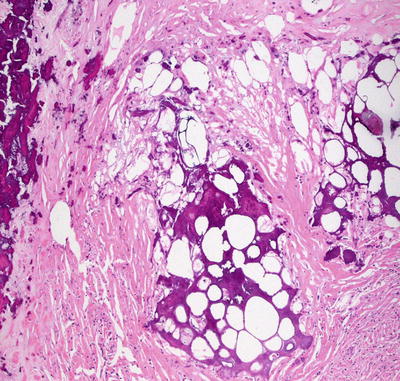

Even though the pathogenesis differs, the histologic findings in traumatic fat necrosis are identical to those described in factitial panniculitis [42, 46]. A lobular panniculitis with abundant fat necrosis and a dense mixed inflammatory infiltrate characterizes traumatic panniculitis (Figs. 9.12, 9.13 and 9.14). Rare cases develop a pseudomembrane that lends a lobulated appearance to the neutrophil-rich inflammatory infiltrate [47]. This pseudomembrane is likely a result of necrotic adipocytes.

Fig. 9.13

Fat necrosis and a mixed inflammatory response are seen in cases of traumatic fat necrosis

Fig. 9.14

Dystrophic calcification secondary to necrosis of adipocytes is a common finding in late stage lesions of traumatic fat necrosis